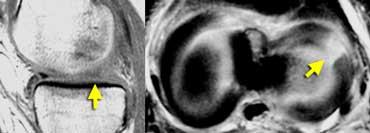

Dấu hiệu sụn chêm rỗng

Khi có rách xuyên tâm hoàn toàn, hai mảnh sụn chêm có thể bị tách rời hoàn toàn.

Điều này có thể dẫn đến hình ảnh khoang sụn chêm rỗng hay còn gọi là dấu hiệu sụn chêm rỗng (mũi tên).

TRÁI: Hình ảnh sụn chêm vắng mặt hoặc rỗng trên mặt phẳng đứng dọc. PHẢI: Hình ảnh mặt cắt ngang cho thấy rách xuyên tâm hoàn toàn dẫn đến khuyết hổng sụn chêm.

Nếu khảo sát một đường rách xuyên tâm hoàn toàn trực tiếp dọc theo chiều dài của đường rách, bạn sẽ thấy hình ảnh sụn chêm vắng mặt hoặc rỗng.

Các đường rách xuyên tâm hoàn toàn này mở ra và tạo ấn tượng rằng có một phần sụn chêm bị thiếu.

Tuy nhiên, bạn sẽ không tìm thấy mảnh sụn chêm bị di lệch.

Đây đơn thuần chỉ là sự tách rời của các phần sụn chêm.